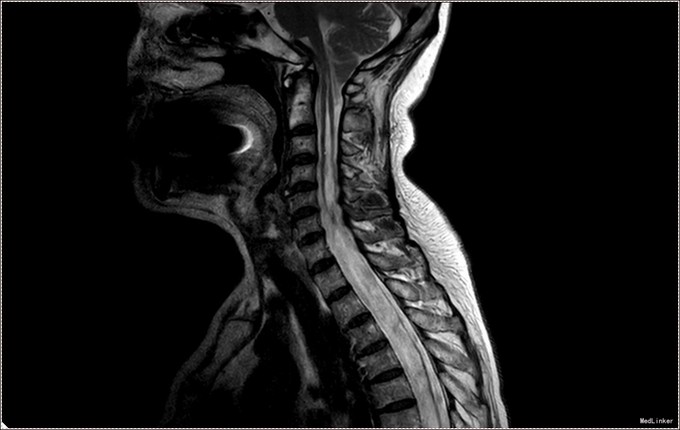

入院查体:神清语明,问答准确,查体合作,精神状态良好。双侧瞳孔等大正圆,D≈3.0mm,双侧眼球活动自如,对光反射灵敏。双下肢肌力减退,肌力三级,肌张力正常。双上肢肌力正常,活动自如。四肢感觉减退,可见多处烫伤瘢痕。双巴氏征(-)。 颈椎MR提示小脑扁桃体下疝畸形,脊髓空洞症(C1-T6);颈椎管狭窄,颈椎间盘膨出(C3-C6)

患者诊断明确,完善术前检查。行枕下减压,扩大修补硬膜,颈髓空洞穿刺。术后予常规治疗。复查颈椎MR提示小脑扁桃体减压充分,脊髓空洞略缓解。但术后3日起发热,行腰穿提示椎管内感染,行腰池引流1周,拔管出院。出院时患者自述左侧肢体麻木感减轻,双下肢肌力较入院好转。